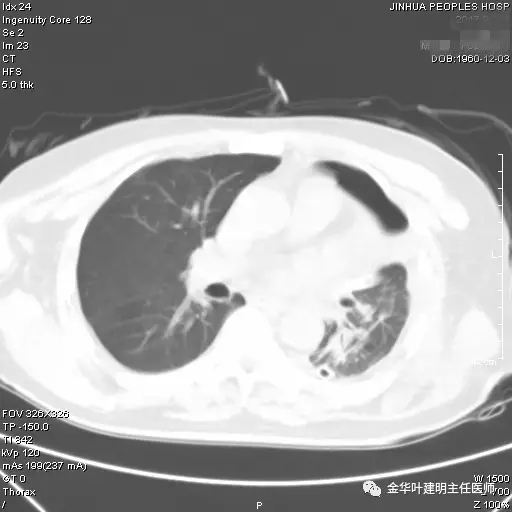

图四示:术后9天胸部CT平扫见左肺下叶膨胀良好